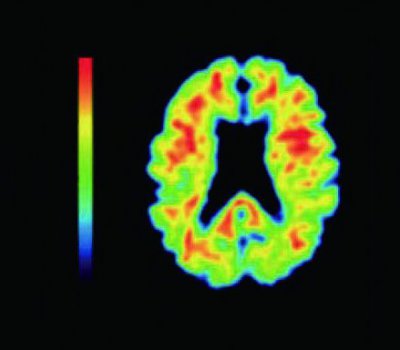

アルツハイマー型認知症を「治す・改善する」ことは難しくても、早い段階で診断できれば「進行をゆるやかにする」ことはできます。 2023年に新たに国内で保険承認されたアルツハイマー型認知症の点滴治療薬「レカ...